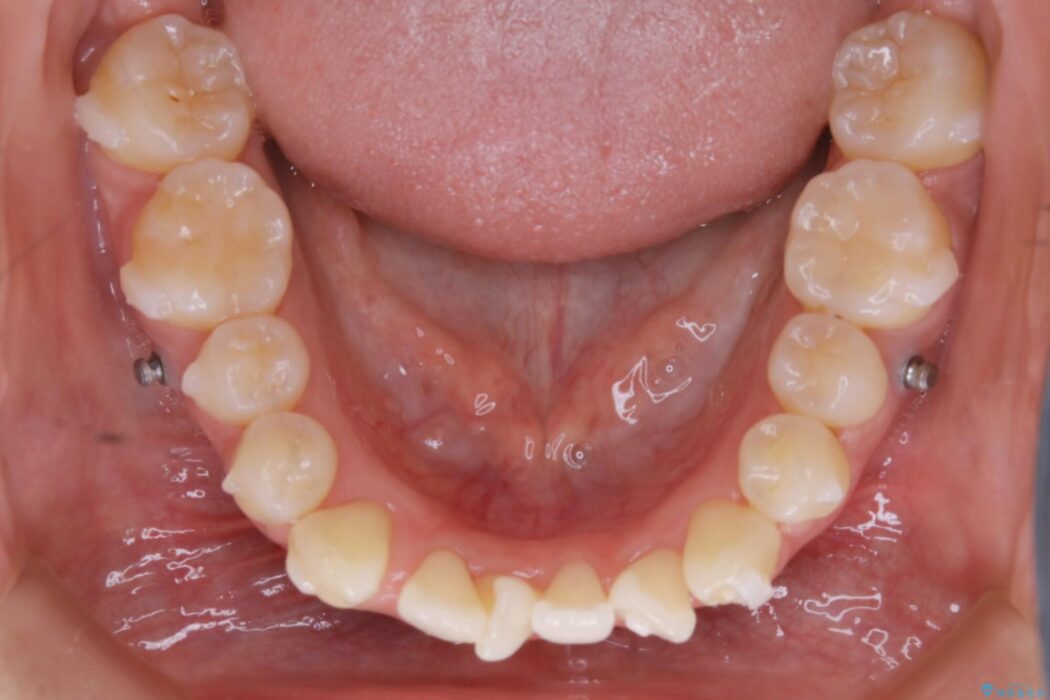

マイクロインプラントとは

マイクロインプラントとは矯正治療で使用する小さなネジのことです。

このネジを支点とし歯を引っ張ることで効率的に動かすことで、治療期間の短縮や従来の矯正治療では難しかった動きも対応が可能になります。

埋入することによる痛みはほとんどありませんが、数日ほど違和感を感じる方はおられます。また治療が終了次第、簡単に取り外すことができます。